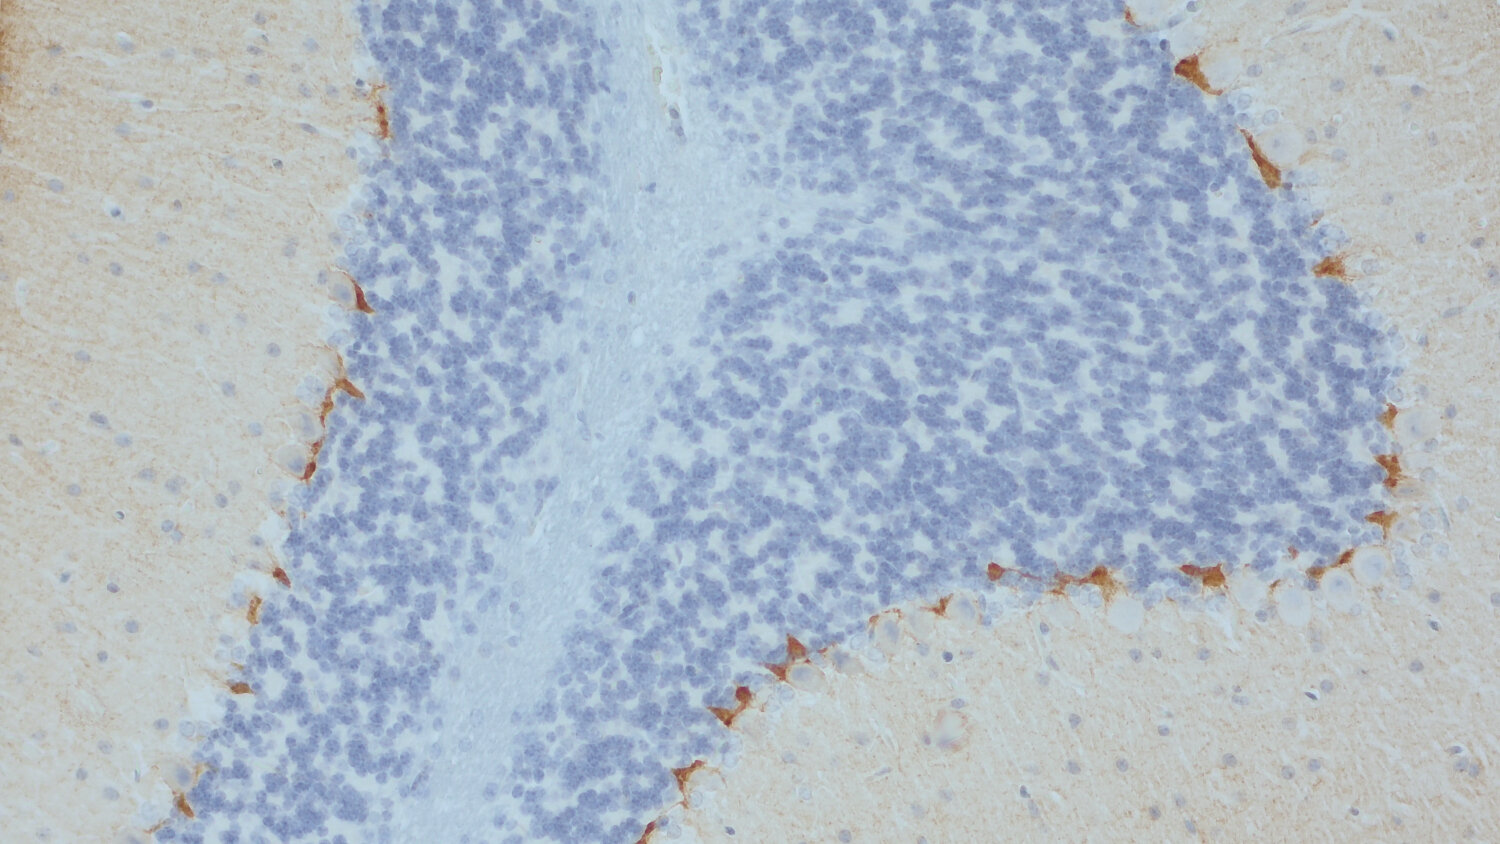

IHC-P: 1 : 500 gallery

Immunohistochemistry (IHC-P) of formalin fixed, paraffin embedded (FFPE) tissue (some antibodies require special antigen retrieval steps, please refer to the ”Remarks” section). Immunoreactivity is usually revealed by fluorescence or a chromogenic substrate.